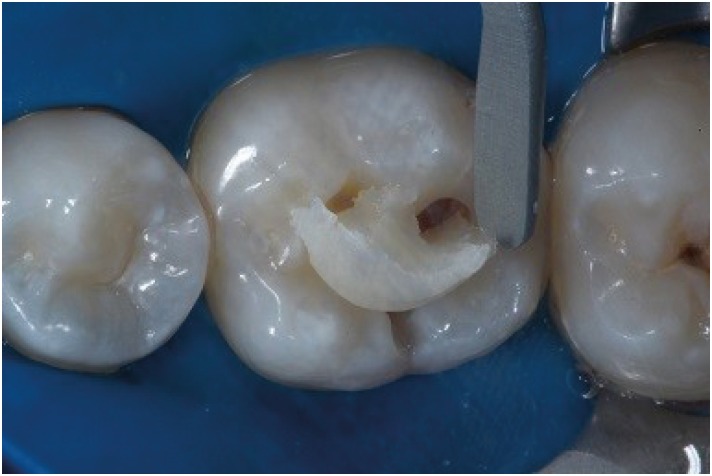

Figure 3

Class I cavity prepared with spherical bur.

rde-45-e9-g003.jpg

Figure 4

After phosphoric acid and adhesive layer placed, Bulk Fill composite resin as placed in the cavity with one increment.

rde-45-e9-g004.jpg